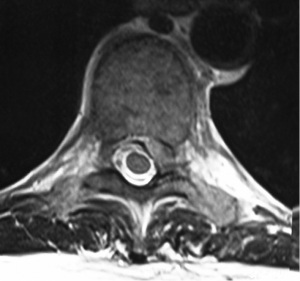

A 62-year-old female presented with a 3-week history of severe left lower thoracic radicular pain. The patient had no neurological deficit on examination. She had no medical comorbidities and was a non-smoker. Initial chest CT and ultrasound were unremarkable. MRI thoracolumbar scan showed an acute, moderate sized, left sided T9-10 foraminal soft disc prolapse extending superiorly into the left T9-10 foramen with significant compression of the exiting left T9 nerve root (Figure 4). The patient was unresponsive to opiate analgesia, pregabalin (Lyrica®, Pfizer, New York, NY, USA) and CT guided left T9 transforaminal epidural nerve root injection. The patient underwent a left sided transpleural T9-10 LIF. Following formal discectomy, a ball tipped blunt hook was inserted superiorly into the T9-10 foramen for removal of extruded disc fragments. A standalone interbody cage (6×16×40 mm3, zero degree, CoRoent XL-T) was placed. EBL was less than 50 mL. A chest tube was not required. Postoperative chest radiography excluded pneumothorax. CT showed satisfactory prosthesis placement at T9-10 with no residual neural compression (Figure 5). The patient reported reduction in preoperative thoracic pain (VAS 9/10 to 5/10), further improved to 2-3/10 with a CT guided T9-10 epidural injection. She was discharged to home 5 days after surgery. At 3 months postoperative, the patient continued to exhibit mild persistent neuropathic thoracic pain requiring paracetamol and pregabalin 75 mg daily, but had returned to part-time work duties. At 6-month follow-up she had solid interbody fusion, confirmed on CT, and had resumed full-time work. At 24 months follow-up the patent reported further improvement in pain (VAS 1-2/10); her ODI (56 to 24), PCS (33 to 48) and MCS (44 to 62) were also improved.